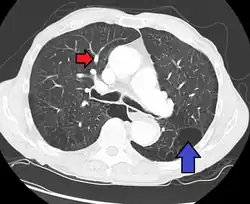

CT scan

Signs of pulmonary hypertension on CT scan of the chest are:

- Enlargement of the pulmonary trunk (measured at its bifurcation). It is, however, a poor predictor of pulmonary hypertension in patients with interstitial lung disease.[63]

- A diameter of more than 27 mm for women and 29 mm for men is suggested as a cutoff.[63]

- A cutoff of 31.6 mm may be more statistically robust in individuals without interstitial lung disease.[63]

- Increased ratio of the diameter of the main pulmonary artery (pulmonary trunk) to the ascending aorta (measured at its bifurcation).

- Increased diameter ratio of segmental arteries to bronchi. This finding in three or four lobes, in the presence of a dilated pulmonary trunk (≥29 mm), and absence of significant structural lung disease confers a specificity of 100% for pulmonary hypertension.[63]

- Mural calcification in central pulmonary arteries is most frequently seen in patients with Eisenmenger's syndrome.[63]